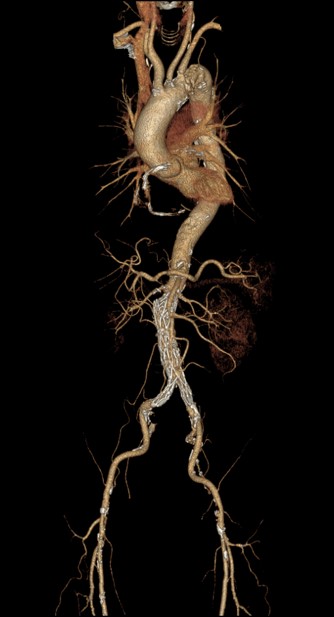

当院では冠動脈CTA撮影時にDelayで大血管のアクセスルート評価も行っております。大動脈に解離や瘤、もしくは壁在血栓等の確認を一度の検査で行っておりますが、冠動脈CTAの際に使った造影剤の造影コントラストでは、Delay撮影時にやや造影効果が不十分となっておりました。患者負担を考慮し、あえて大動脈の評価のための造影剤追加投与は行っていませんが、TEDLの機能によって120kVpで撮影するだけで、Dual Energyで得られるような低keV相当の造影コントラストが取得でき、まさにDual Energyと同等の効果を得られています。病院としても、過剰な造影剤使用量を抑えられることで、DPCによる算定できないコストの削減にもつながっていると思います。まさに、患者目線・医師目線・病院目線でTEDLのメリットを感じることができています。

冠動脈CTA撮影後のDelayでのAorta撮影の画像を下記に提示します。通常の120kVpで撮影された画像と比較して、TEDLの画像の方が造影コントラストが得られますので、当院では、全例でTEDLを活用しています。

実際に、冠動脈CTA施行時にAAAとCIAに壁在血栓のある症例ですがdelay撮影でも十分な存在確認ができています。

Ascend_ayase13.png

TEDLを活用した血栓評価